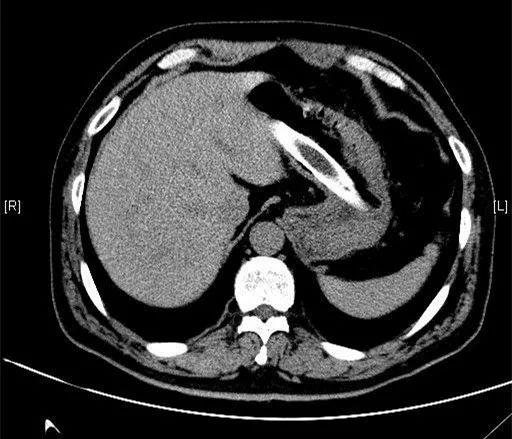

一节、二节、三节……总共有五节,其中四节是折断的衣架,一节是塑料管。这些从病人胃内取出的异物直径约为0.8厘米至2厘米,长度11-15厘米。

该患者今年58岁,3个月前,他将塑料衣架折断后吞进肚子里,同时塞进去的还有一节塑料管。近日该患者感觉肚子隐痛才来医院就诊。经CT扫描和病人自述,大家都惊呆了。